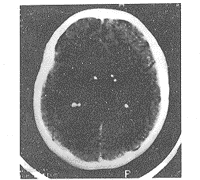

结节性硬化症三家系11例分析

结节性硬化症三家系11例分析中国神经免疫学和神经病学杂志 1999年第4期第6卷 论 著作者:薛官英 韩晓东 任思庆 岳学旺单位: